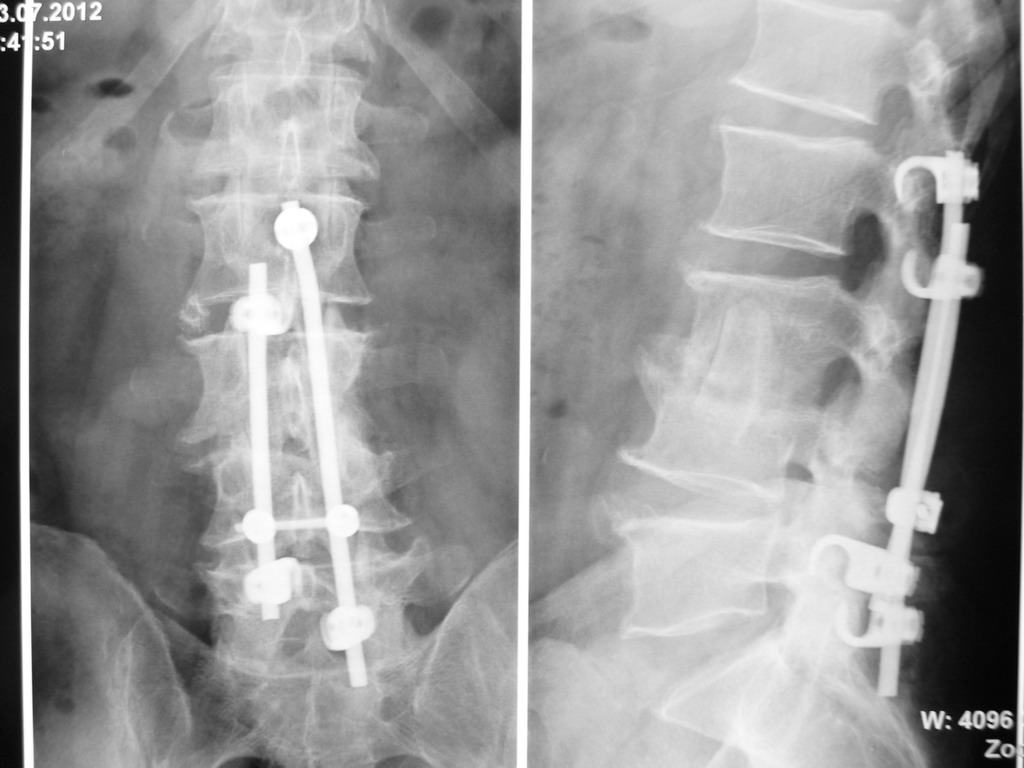

Для радикального лечения необходима хирургическая операция – задняя внутренняя фиксация позвоночника, а при выраженных разрушениях позвонкови образовании гнойных затеков и передние операции с резекцией тел позвонков и санацией патологического очага. В дальнейшем проводится антибиотикотерапия и динамическое наблюдение. К сожалению, отказ от активной хирургической тактики лечения приводит порой к непоправимым осложнениям.